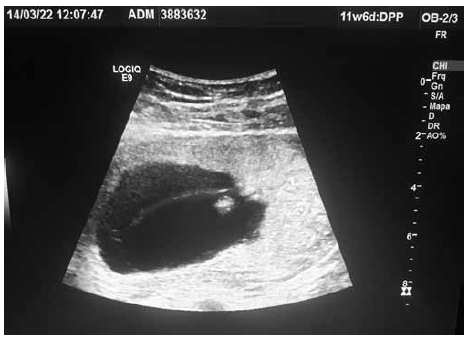

Figura 2

Com base nas figuras 1 e 2, o melhor manejo pré-natal para a paciente é:

Paciente com IG de 12 semanas pela DUM veio à medicina fetal para realização de seu primeiro ultrassom obstétrico. Identificadas as figuras 1 e 2 (em ângulos e posições diferentes), conforme ilustrado.

Com base nas imagens em conjunto, assinale o diagnóstico correto é: